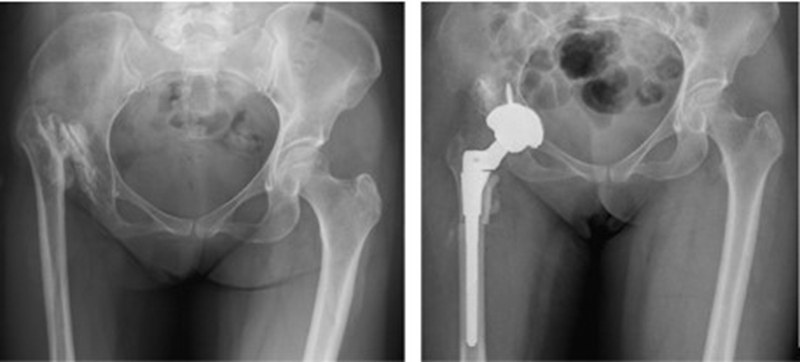

2、假体选择

①保留畸形:表面髋置换、短柄假体。

②让骨骼适应假体:股骨截骨。

③让假体适应畸形:组配式假体

④hybrid、水泥柄。

③近端的重建:纠正性截骨,短缩截骨。

纠正性截骨的要求是:

①在畸形最严重的部位纠正对线不良;

②最大限度保留骨质;

③截骨部位牢固固定;

④使用长柄假体跨越截骨端。